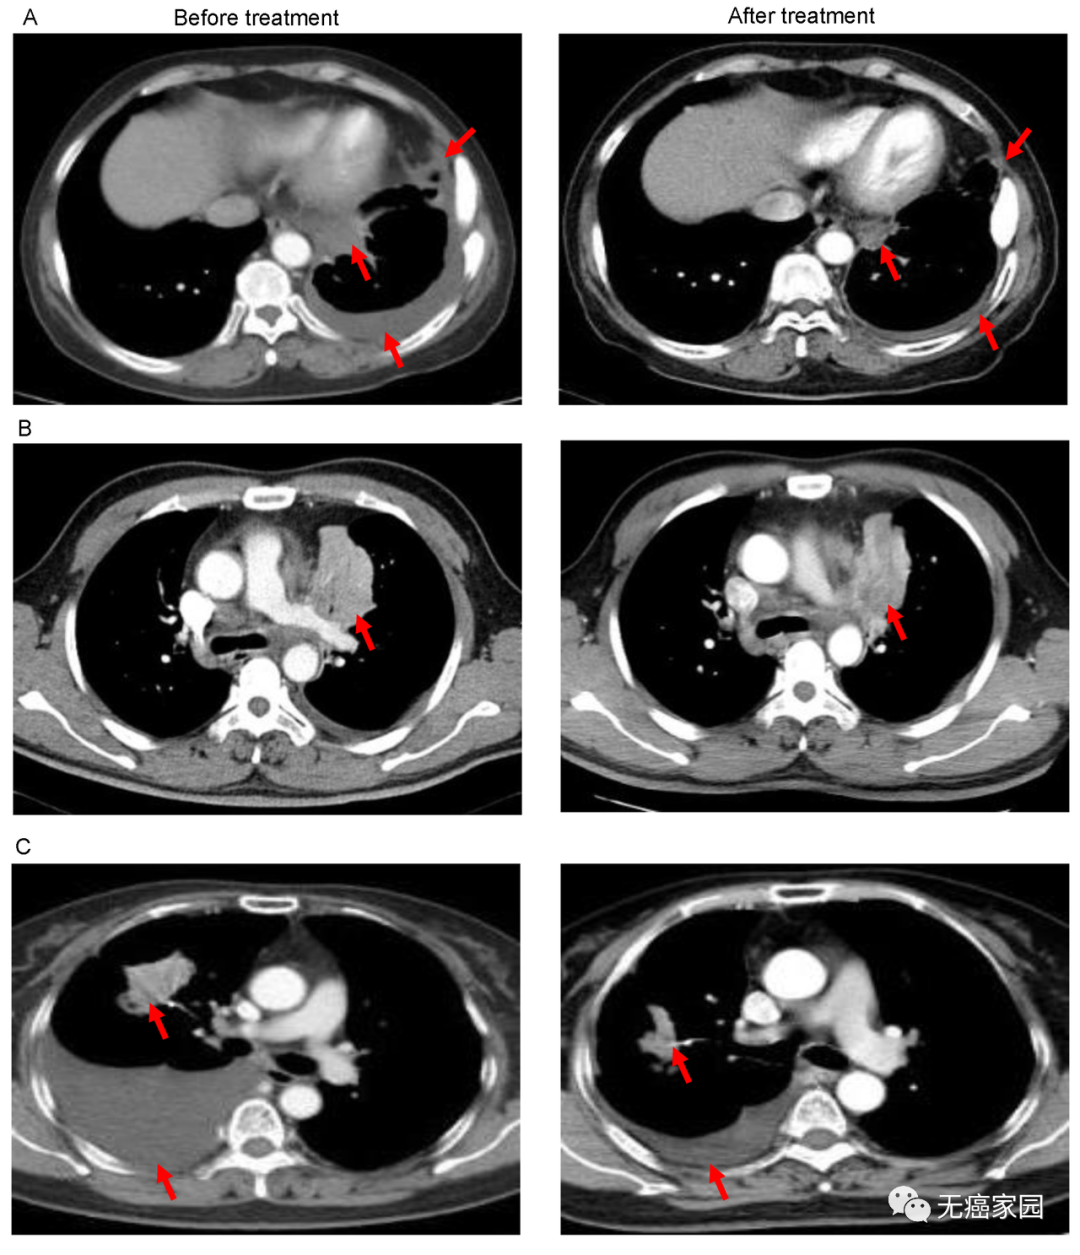

图A中患者1在输注CAR-T细胞后,通过CT扫描显示其胸腔积液减少,转移性肺门淋巴结和胸膜结节轻度缩小(箭头)。

图B中CT图像显示患者8的原发性肿瘤缩小(箭头);

图C中CT检查发现CAR-T治疗后患者9的胸腔积液吸收和肺部病变明显消退。

图中显示结束治疗后,患者的肿瘤完全消失